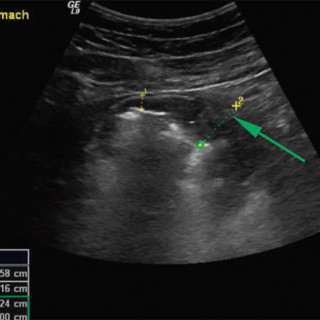

HACEK er et akronym som refererer til en gruppe taksonomisk ulike bakterier med en rekke fellestrekk. Det står for Haemophilus parainfluenzae, Aggregatibacter (A aphrophilus, A actinomycetemcomitans), Cardiobacterium spp., Eikenella corrodens og Kingella kingae (1, 2). Alle disse har en tendens til å forårsake endokarditt, men de var tidligere lite kjent fordi de er vanskelige å få til å vokse. HACEK-endokarditt havnet derfor i gruppen kulturnegative endokarditter. Fremdeles forblir mange av disse endokardittene kulturnegative. Bakteriene er små, gramnegative staver tilhørende den...